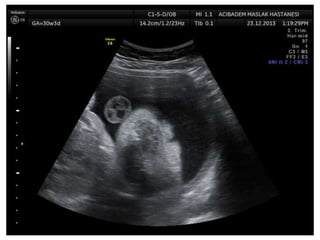

Amniotic band sequence:

Amniotic band sequence refers to a highly variable

spectrum of congenital anomalies that occur in

association with amniotic bands

Anomalies include:

Craniofacial abnormalities — eg, encephalocele, exencephaly,

clefts, which are often in unusual locations; anencephaly.

Body wall defects (especially if not in the midline), abdominal or

thoracic contents may herniate through a body wall defect and

into the amniotic cavity.

Limb defects — constriction rings, amputation, syndactyly,

clubfoot, hand deformities, lymphedema distal to a constriction

ring.

Visceral defects — eg, lung hypoplasia.

Other — Autotransplanted tissue on skin tags, spinal defects,

scoliosis, ambiguous genitalia, short umbilical cord due to

restricted motion of the fetus